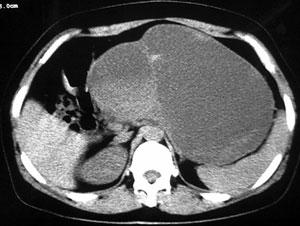

女44腹部不适

接着ct4478平扫

胰腺体尾部囊实性占位,有分隔.内无脂肪及钙化等组织.胰腺囊腺瘤.

胰腺体尾部囊实性占位,境界清晰,内有间隔呈多房性,周围无炎性改变,考虑胰腺囊腺瘤。